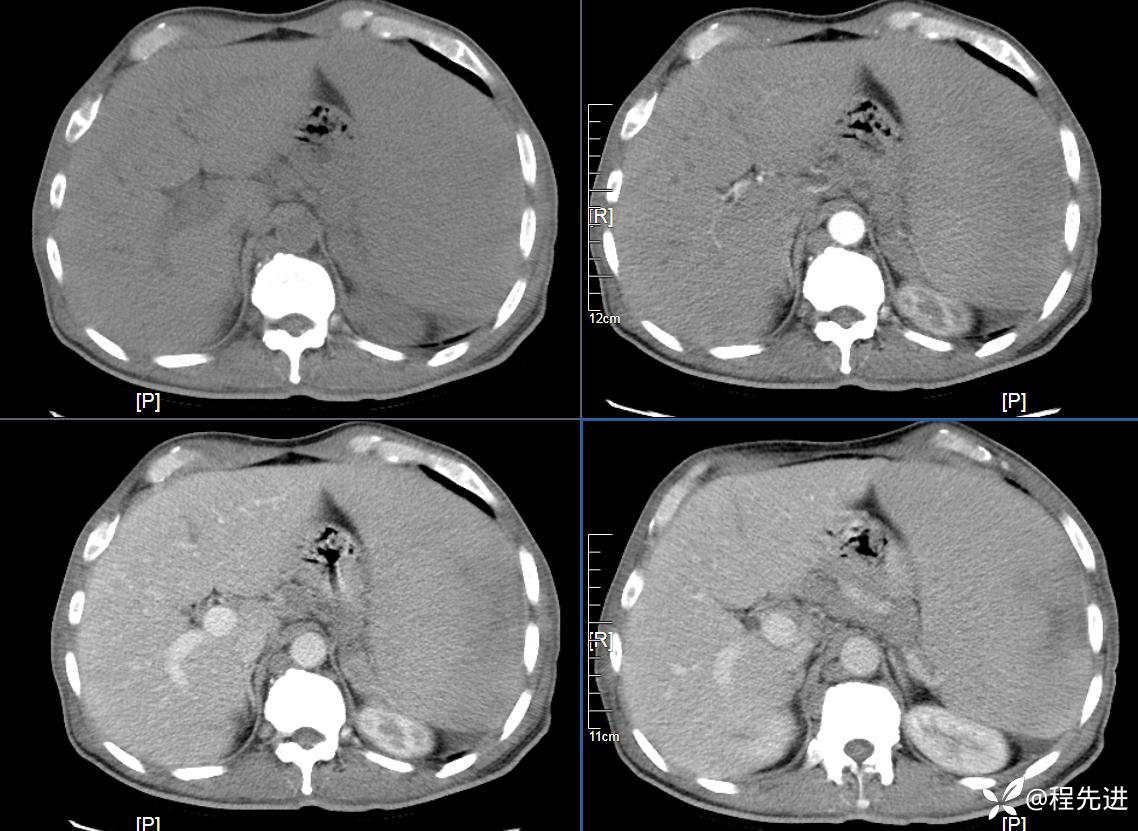

患者性别:男

患者年龄:59岁

简要病史:体检发现脾脏肿大半月

CT平扫及增强3期: